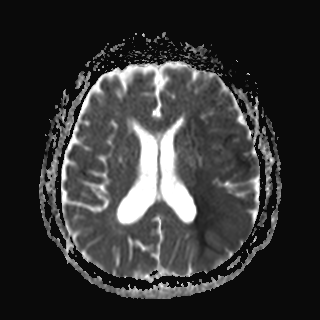

처음 시행한 환자의 brain DWI 검사이다.

환자의 brain DWI(뇌 확산영상)에서 좌측 MCA territory(중뇌동맥 영역)에 급성기 뇌졸중이 발생한 것을 확인할 수 있었다.

이정도로 큰 크기의 경색이면 대부분 큰 뇌동맥이 막혀서 생기는 질환(Large artery disease)이 많다.